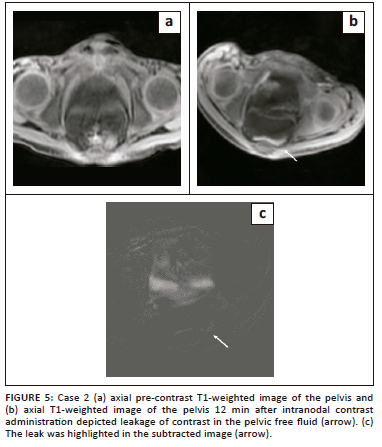

Dynamic contrast enhanced MR lymphangiography was performed after ultrasound guided cannulation of the inguinal lymph nodes. Dilute gadolinium-based contrast was injected on the MRI table. The scan revealed dilated bilateral lumbar lymphatics that were opacified within a few minutes of contrast injection with non-opacification of the cisterna chyli (Figure 4b). Contrast accumulation was seen in the pelvic free fluid on subsequent images (Figure 5). The CLLs remained unopacified on delayed phase imaging due to compression by enlarged retroperitoneal lymph nodes (Figure 4c and d).

In both presented cases, intranodal DCE-MR lymphangiography was performed. The procedure involved initial routine MRI abdomen and pelvis sequences using a 3 tesla MRI scanner along with heavily T2-weighted images for delineation of the cisterna chyli and thoracic duct. Following this, the patient was shifted outside the MRI unit for nodal cannulation under ultrasound guidance. Using an aseptic technique, 1% lidocaine was injected intradermally at the area of interest, following which, bilateral superficial inguinal lymph nodes were cannulated using a 22-gauge needle followed by saline injection. The lymph nodes became more prominent after saline injection and after ensuring adequate placement, the needle was connected to 10-cm long tubing attached at its end to a three-way stop cock. A syringe containing a gadolinium and saline solution ratio of 1:1 was connected to the stop cock. The gadolinium dosage was 0.1 mmol/kg. The patient then returned to the MRI table and a mask T1-weighted image of the chest and abdomen was obtained prior to the injection of gadolinium via the stop cock. Multiple axial and coronal post-contrast T1-weighted (VIBE) images of the abdomen followed by the chest were obtained at every 1-min interval for about 30 minutes, and subtracted images were generated to enhance the sensitivity for detecting intraperitoneal contrast leakage.